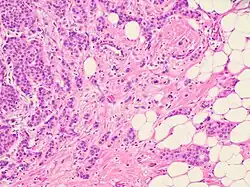

Collective cell migration has been observed in the development and progression of breast and endometrial cancer, prostate cancer, colorectal cancer, large-cell lung carcinoma, rhabdomyosarcoma, melanoma, as well as most squamous cell carcinomas.[2]

In the case of collective migration, cancer cells, being a part of the tumor mass or detaching from it in the form of multicellular groups, penetrate into the surrounding tissues and form thin, short chords, clusters, stripes and wide fields, as well as structures with lumen, that indicate a wide variety of structural elements involved in tumor invasion.[2]

Despite the structural diversity of the primary breast tumor, five main types of morphological structures can be distinguished: alveolar, trabecular, tubular and solid structures, and discrete groups of tumor cells. The alveolar structures are tumor cell clusters of round or slightly irregular shape. The morphology of the cells that form this type of structures varies from small cells with moderate cytoplasm and round nuclei to large cells with hyperchromatic nuclei of irregular shape and moderate cytoplasm. The trabecular structures are either short, linear associations formed by a single row of small, rather monomorphic cells or wide cell clusters consisting of two rows of medium-sized cells with moderate cytoplasm and round normochromic or hyperchromatic nuclei. The tubular structures are formed by a single or two rows of rather monomorphic cells with round normochromic nuclei. The solid structures are fields of various sizes and shapes, consisting of either small cells with moderate cytoplasm and monomorphic nuclei or large cells with abundant cytoplasm and polymorphic nuclei. Discrete groups of cells occur in the form of clusters of one to four cells with variable morphologies.[2]

The different morphological structures of breast tumors correspond to certain types of invasion. Therefore, alveolar, trabecular, and solid structures that are characterized by the presence of cell-cell contacts may be referred to morphological manifestations of collective migration, while discrete groups of tumor cells may be referred to manifestations of individual migration. The first batch of data obtained in a study of the expression of cell adhesion genes confirms this hypothesis. For example, there was a decrease in the activity of the genes of cadherins, which are responsible for cell-cell contacts, in the order: solid – alveolar and trabecular structures – discrete groups of tumor cells. In this case, the number of expressed genes of integrins involved in the adhesion of tumor cells to the extracellular matrix was reduced in the order: solid and alveolar – trabecular structures – discrete groups of tumor cells.[2]